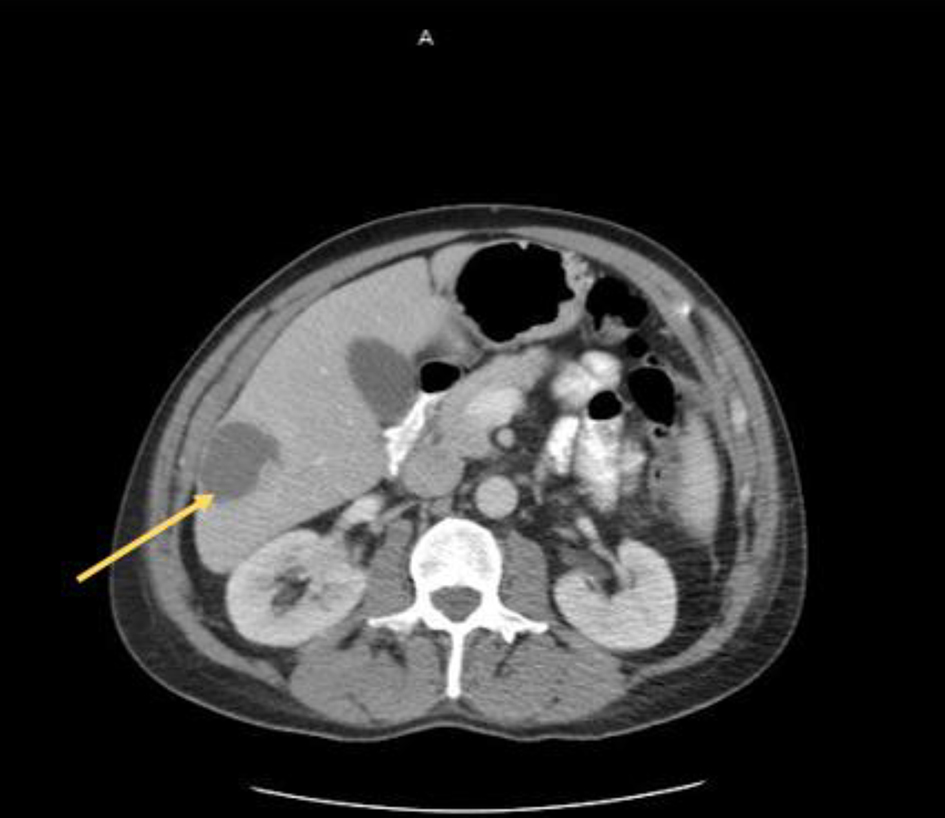

At initial presentation, his vital signs were as follows: blood pressure: 120/68 mm Hg; heart rate: 101 beats per minute; respiratory rate: 18/min; body temperature: 37.8 °C; oxygen saturation: 95% room air. Physical examination demonstrated mild tenderness in the right upper quadrant and right flank area. The patient did not have lymphadenopathy, masses or hepatosplenomegaly. On initial complete blood cell count, the white blood cell count was 13,000/µL (range: 4,500 - 11,000/µL). In addition, complete metabolic panel showed an elevated aspartate aminotransferase of 98 IU/L (range: 10 - 42 IU/L), alanine aminotransferase of 109 IU/L (range: 10 - 60 IU/L), alkaline phosphatase of 219 IU/L (range: 38 - 126 IU/L) and total bilirubin 2.6 mg/dL (range: 0.2 - 1.3 mg/dL). Hepatitis panel was negative. His erythrocyte sedimentation rate (ESR) and C-reactive protein (CRP) levels were elevated, 34 mm/h and 25.98 mg/dL, respectively. Blood and urine cultures were obtained. The patient was sent for right upper quadrant abdominal ultrasound which showed a heterogenous nodular liver with two complex masses in the right lobe, measuring 4.0 × 4.0 cm and 3.6 × 3.6 cm. The patient was started on intravenous (IV) piperacillin/tazobactam for empiric coverage. Subsequent computed tomography (CT) of the abdomen and pelvis with IV contrast revealed multiple low-attenuation lesions involving the entire right hepatic lobe, suspicious for hepatic abscesses versus cystic metastases. The largest lesion involved the inferolateral aspect of the right lobe, measuring 4.2 cm in greatest diameter (Fig. 1). A notable 4.0 × 5.7 cm small bowel mesenteric mass was also identified on imaging (Fig. 2). After discussion with the patient, surgical exploration with liver biopsy was planned.

![]() Click for large image | Figure 1. Liver lesion (arrow) identified on axial CT scan of the abdomen and pelvis. CT: computed tomography. |